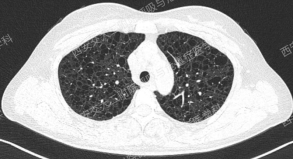

上图所示肺部多发囊性病变,双肺广泛分布,直径在2-10mm之间,壁薄,囊壁间组织相对正常。结合育龄期女性等临床资料,不难诊断淋巴管平滑肌瘤病(LAM)。对疑似LAM的女性的初步评估还应包括血管平滑肌脂肪瘤的筛查、淋巴管受累以及是否存在未被诊断的结节性硬化症。该例患者经评估后诊断散发型S-LAM。

该患者肺功能下降达到治疗标准,但患者及家属暂不考虑用药,选择观察,目前随访中。曾咨询乘飞机到拉萨的问题,鉴于症状稳定,可乘坐飞机,但不建议上高原。